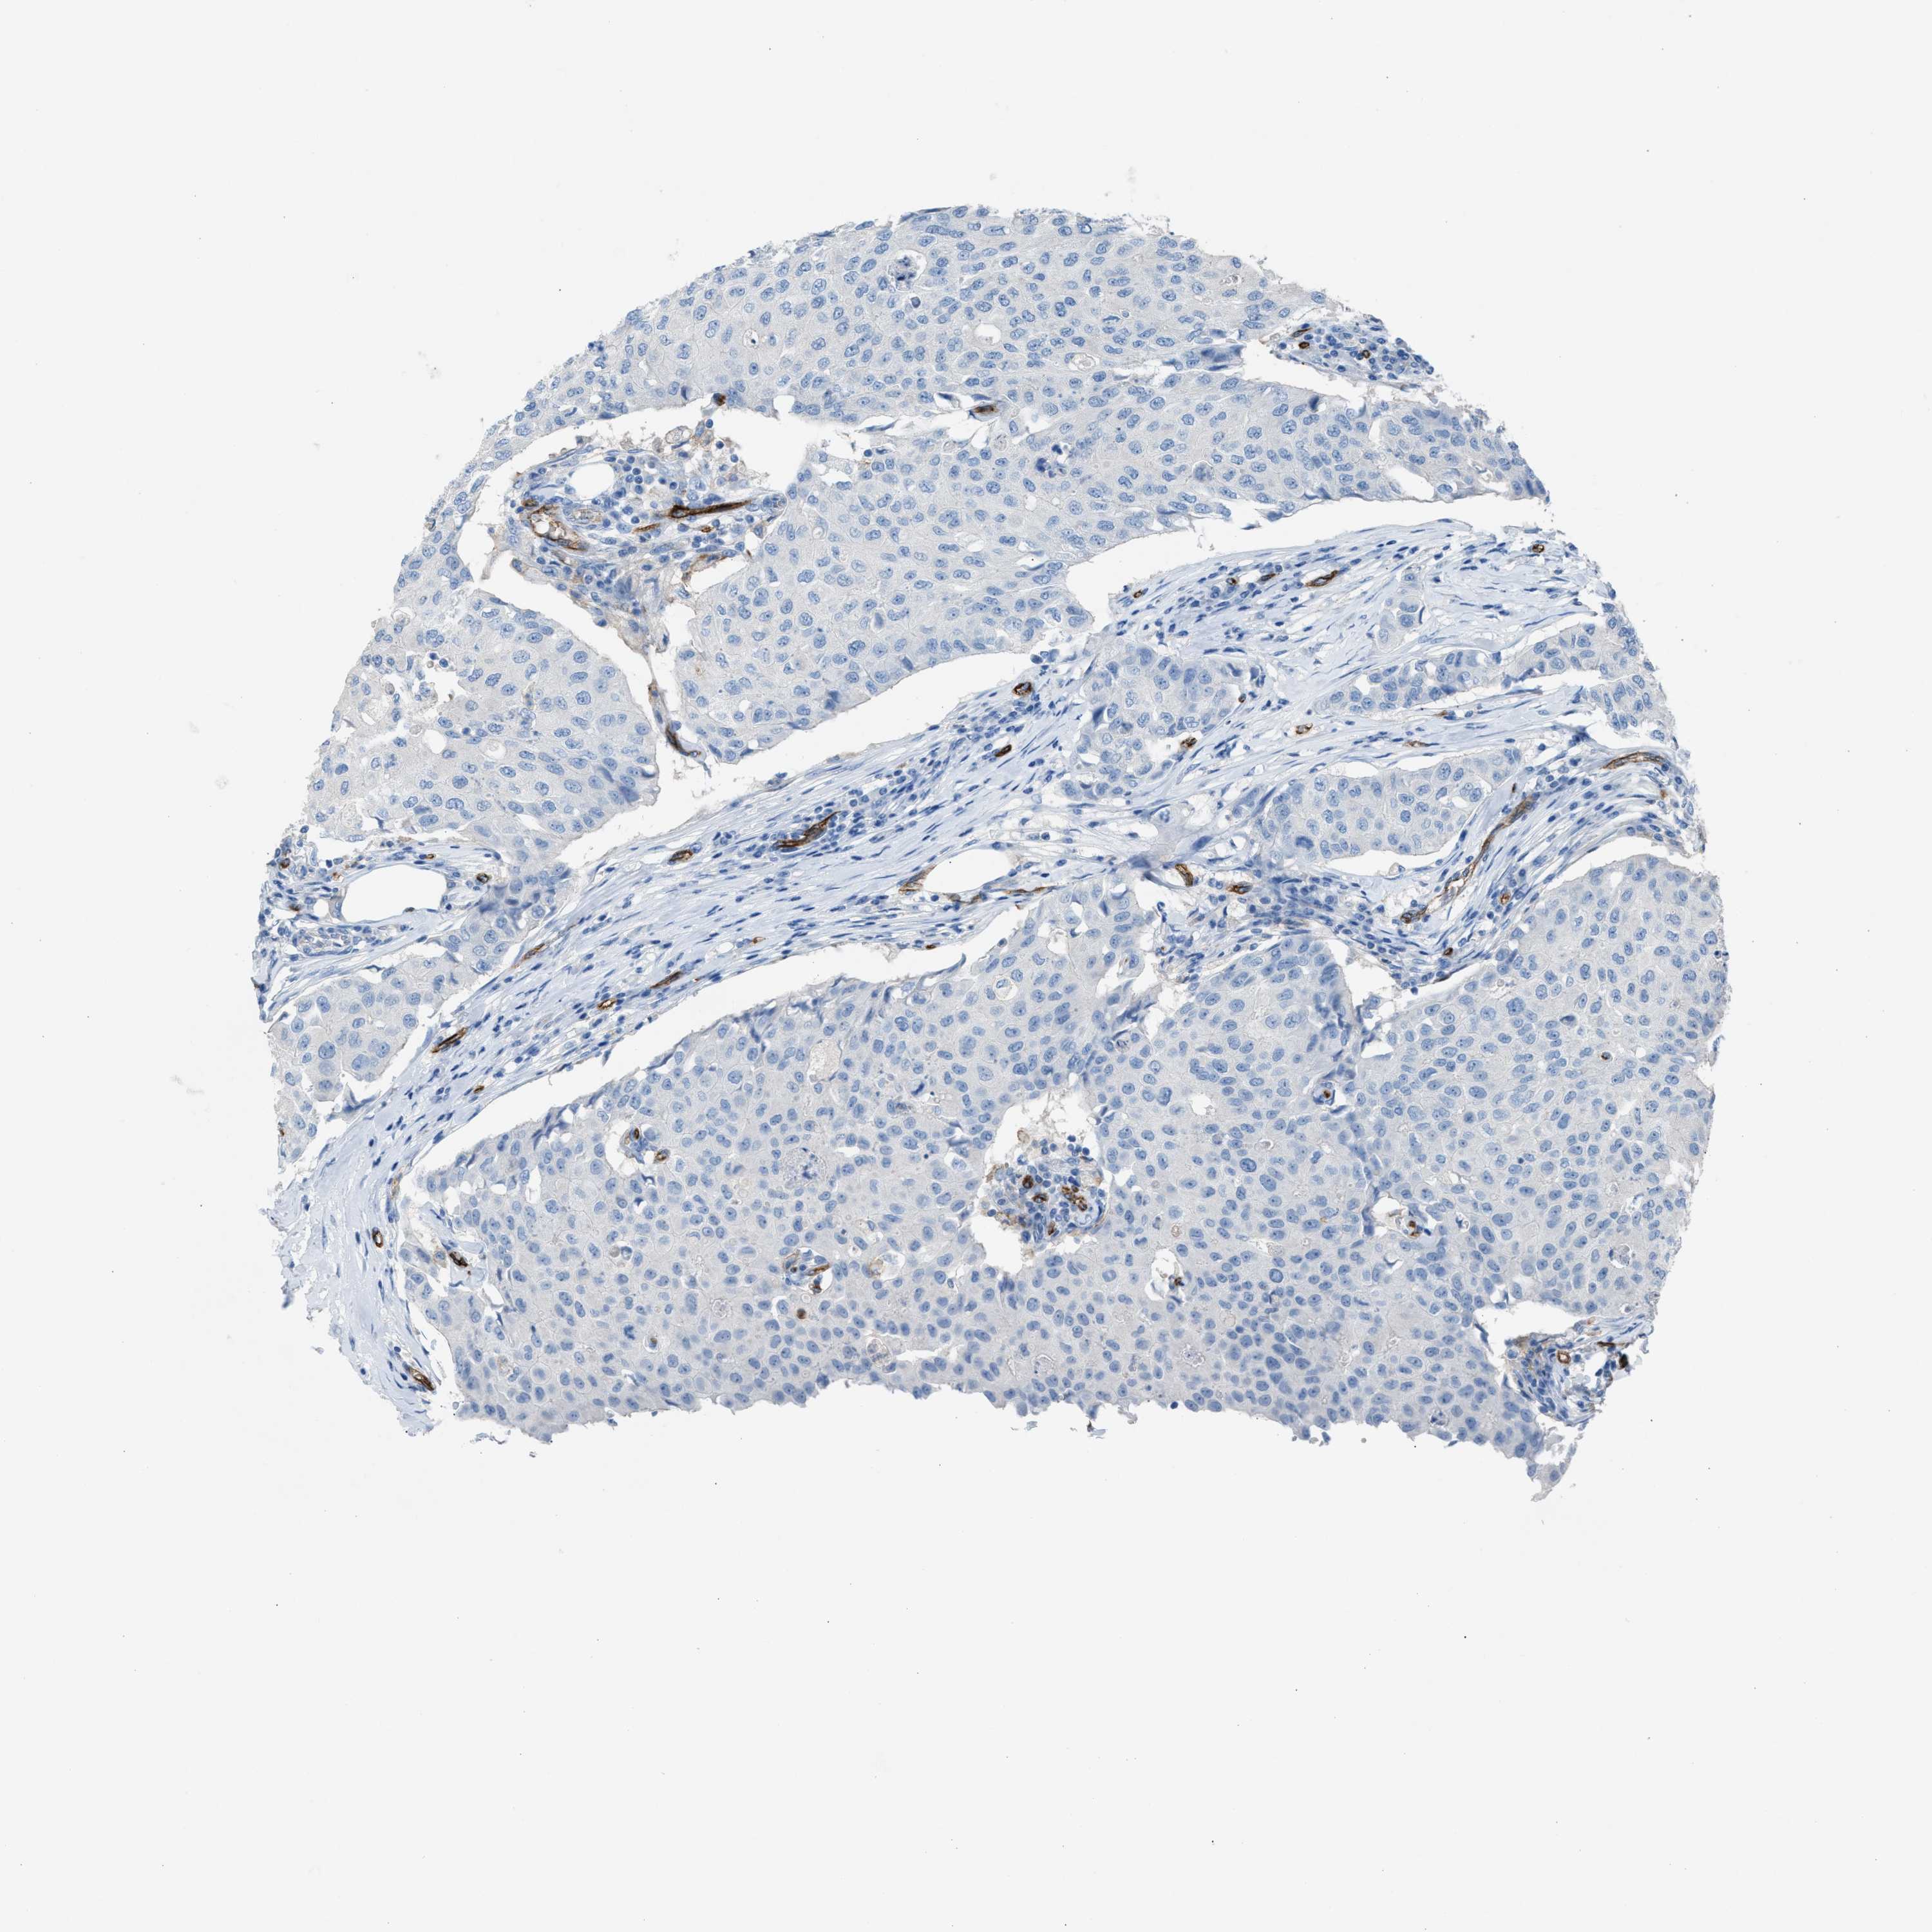

BRCA TCGA BRCA VALIDATION PROTEIN EXPRESSION

ANTIBODIES

AND

VALIDATION